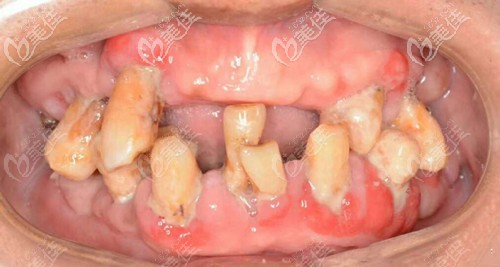

做種植牙前牙齒缺失、牙齒松動、牙周病較厲害

邱醫(yī)生說我姥爺?shù)目谇恍l(wèi)生狀況不太好,牙周石比較厲害,牙齒缺失,雖然現(xiàn)在口內(nèi)還10顆牙齒,也開始出現(xiàn)了松動的跡象,陸續(xù)的牙齒都會脫落,沒有其他方案可以選擇了。